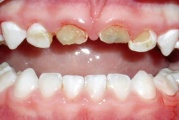

Emaili hüpoplaasiad

muutused hammaste kujus

Amelogenesis Imperfecta